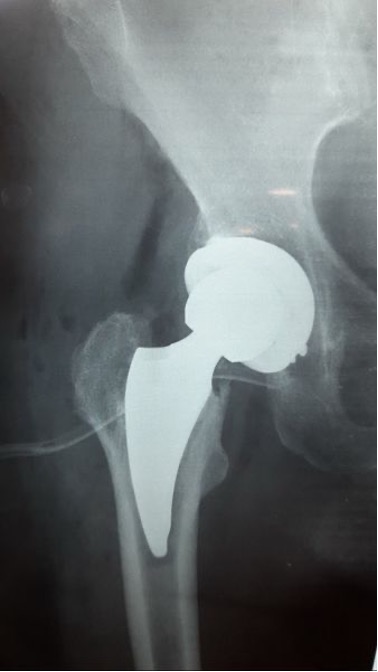

Ακτινογραφία πριν και μετά το παρεκτοπισμένο υποκεφαλικό κάταγμα ισχίου:

Ελάχιστα επεμβατική μέθοδος ALMIS (τροποποίηση N. Χριστοδούλου) με αναισθησία μόνο των κάτω άκρων (υπαραχνοειδή), με πολύ μικρή τομή δέρματος και μαλακών μορίων. Σύντομη επέμβαση με σχεδόν μηδαμινή απώλεια αίματος και φυσικά χωρίς μετάγγιση αίματος ή ανάγκη καθετήρα κύστεως, χρήση μικρών εμφυτευμάτων ελάχιστης οστικής κάκωσης με δυνατότητα μόνιμης περιπροθετικής οστεογένεσης, χωρίς χρήση βιδών ή χρήση ακρυλικού πολυμερούς.

Ειδική συρραφή της μικρής τομής δέρματος με βιο-απορροφήσιμα ράμματα που δεν χρειάζονται αφαίρεση.

Άμεση έγερση και βάδιση την ίδια ημέρα.